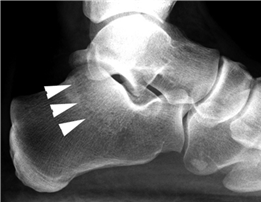

Clinical & Radiographic Imaging Archive

Clinical Image